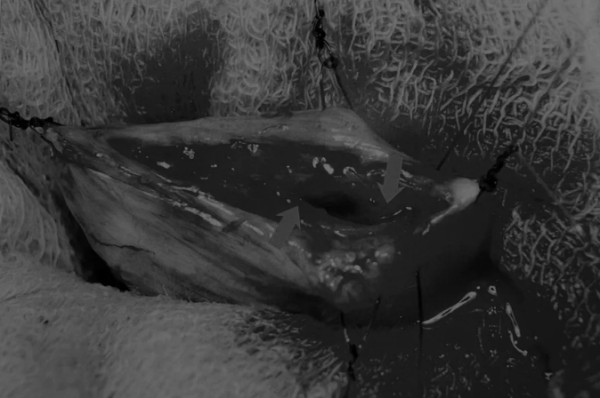

图8 这张图显示了通过导尿管注射的盐水,在缝合的切口处没有液体渗漏

关膀胱后,将无菌盐水注入膀胱腔内,检查是否有渗漏(图8)。